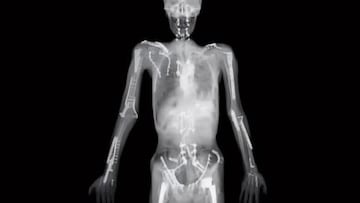

La imagen que circula en redes con un cuerpo lleno de tornillos y placas no pertenece a Travis Pastrana. El propio piloto lo aclara en su canal de YouTube, Channel 199: existe una radiografía extrema atribuida a él, pero “no es mi cuerpo, no me lo he roto todo”, explica antes de repasar sus cinco peores accidentes y las lesiones que marcaron su carrera.

Aunque... su auténtica “radiografía” real debe ser igual de brutal. Pastrana detalla, por ejemplo, que ha sufrido 40 fracturas repartidas en siete huesos del pie derecho, además de roturas de tibia y peroné en ambas piernas y varias fracturas de meseta tibial —“tres en un lado y dos en el otro”, precisa— que terminaron en un reemplazo de rodilla. A ello se suman tres roturas de ligamento cruzado anterior en una rodilla y dos en la otra, un reemplazo de cadera, pelvis hecha añicos, clavículas rotas varias veces, costillas fracturadas, un codo operado con 11 años y una muñeca fusionada tras incontables caídas.